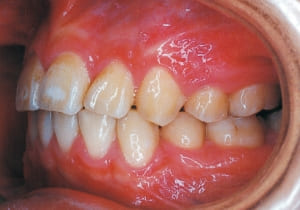

Age at initial visit : 7 y 7 m, male /Protruding upper bite. Open bite. Receding lower jaw. Protruding dual dentition.

1 Initial Visit 2-11-’88

The Class II condition is pronounced, with a significant overjet of 12.5 mm(3). Although the teeth size are large, crowding is relatively mild. The maxillofacial structure has good depth and a robust bone framework(5). The mandible itself is solid , robust gonial angle, but there is significant anterior-posterior displacement relative to the maxilla(ANB 10.0°). While there is no confirmed history of thumb-sucking or similar habits, the lower lip is already pushing up against the maxillary incisors. The cause of this condition is unknown.